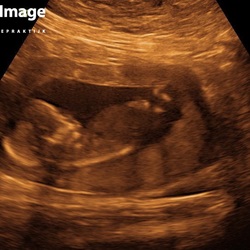

Ik had ook last van pijn bij wat ik dacht mijn eierstokken. Ik ben 12 jaar geleden ook aan mijn eierstok geopereerd, dus een bbz was niet uitgesloten. Op de echo kunnen zien dat toch alles goed was en het toch groei of innestelingspijn is geweest. De steekjes hoeven dus niet altijd iets te betekenen. 😊